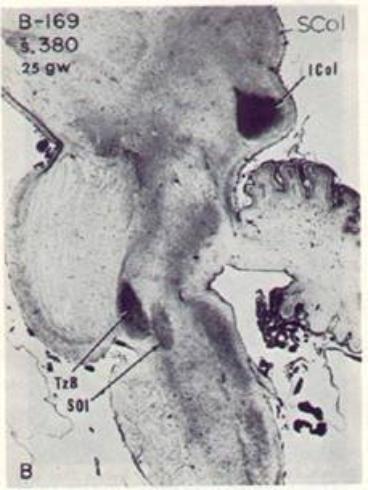

| The brainstem auditory pathway is myelinated earlier in the human fetus than any other circuit of the brain, |

| and essential for learning to speak. |

| Midbrain: |

| ICol -- Inferior colliculus SCol -- Sperior colliculus |

| Lower brainstem auditory nuclei: |

| TzB -- Trapezoid body SOl -- Superior olive |

| (from Yakovlev & Lecours, 1967, with permission from Blackwell Scientific Publications). |